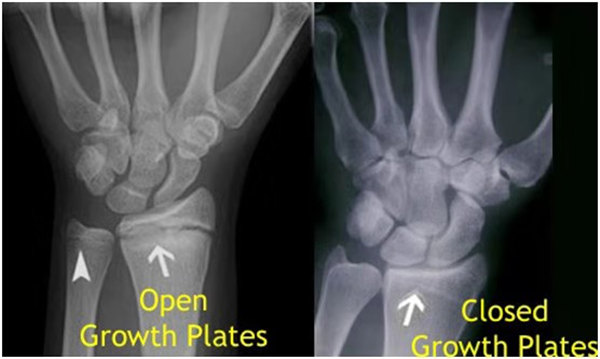

其實(shí)想要了解孩子的生長(zhǎng)發(fā)育情況或者說(shuō)孩子未來(lái)身高的趨勢(shì),測(cè)骨齡是個(gè)好辦法。臨床上通常拍攝兒童的左手正位X光片 , 采用《中華-05》骨齡標(biāo)準(zhǔn)對(duì)手腕骨發(fā)育程度進(jìn)行骨齡評(píng)價(jià)。

我們都知道,人體的高矮是由骨骼的生長(zhǎng)發(fā)育決定的,特別是下肢長(zhǎng)骨。長(zhǎng)骨呈長(zhǎng)管狀,在長(zhǎng)骨的兩端有一種專(zhuān)管骨骼生長(zhǎng)的骺軟骨,它與干骺端之間有一盤(pán)狀軟骨結(jié)構(gòu)稱(chēng)為骺板(線),在幼兒的X光片上表現(xiàn)為一條較寬的透光帶。 (見(jiàn)下圖)

未成年時(shí)隨著年齡的增加骺軟骨端不斷骨化,骨骼就不斷增長(zhǎng)。當(dāng)骨骺線完全閉合時(shí)骨骼就停止生長(zhǎng),個(gè)子也就不再增長(zhǎng)了。一般骨骺端完全閉合的年齡是18~20歲左右。